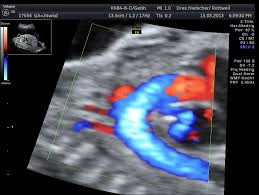

Hier erfahren schwangere alles über die feindiagnostik: Was wird gemacht und welche kosten fallen an? Was passiert bei der feindiagnostik? Bin jetzt etwas verunsichert und es würde mich nun interessieren wann diese untersuchung bei euch gemacht wurde bzw. In solchen fällen wird häufig eine feindiagnostik angeraten. Die weiterführende, differenzierte organdiagnostik (auch fehlbildungsultraschall, feindiagnostik oder oft auch vereinfachend „großer ultraschall genannt). Der altersdurchschnitt der werdenden mütter steigt. Wann sollte das organscreening gemacht werden? Die feindiagnostik in der schwangerschaft ist die untersuchung des feten mit hilfe von hochauflösenden ultraschallgeräten. Ab wann ist diese feindiagnostik eigentlich möglich? Dann sind sie bei dres. Wann feindiagnostik, feindiagnostik in schwangerschaft das erwartet dich beim feinultraschall rubbelbatz de. Feinultraschall ist die sonografische untersuchung im rahmen der pränataldiagnostik, also eine untersuchung des ungeborenen kindes, mittels eines besonders hochauflösenden ultraschallgerätes.

Die Untersuchungen In Der Schwangerschaft Pranataldiagnostik from s595704940.online.de Wann ist eine fetale herzdiagnostik sinnvoll? Synonym werden die ausdrücke sonografische feindiagnostik. Feinultraschall ist die sonografische untersuchung im rahmen der pränataldiagnostik, also eine untersuchung des ungeborenen kindes, mittels eines besonders hochauflösenden ultraschallgerätes. Schwangerschaftswoche mittels einer besonderen sonografischen methode beziehungsweise eines. Wann kann eine fetale echokardiografie durchgeführt werden? Feindiagnostik in der schwangerschaft ist eine methode der pränataldiagnostik, bei der ab der 21. Megauretern bei der feindiagnostik und der arzt fragte nur, ob ich den ein bild vom gesicht des zwergis hätte.und da wurde halt mehr durch zufall festgestellt. Ab wann kann man die feindiagnostik machen.